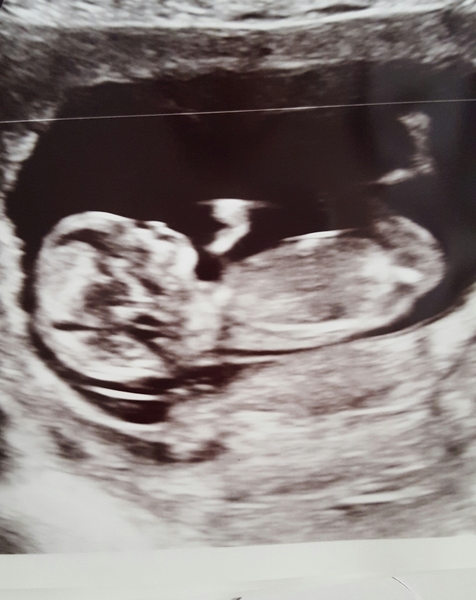

I am 8+6 weeks with dc2. All a bit of a surprise really as while we were 'trying' we were't really and it seems a bit lucky if that makes sense?

I had a bit of spotting at week 6 and again at week 7. The first time really shocked me and I cried for ages. Second time I was more relaxed. I must admit to being more anxious about my scan than I was last time. It is booked for the 15th December so until then I am living by the mantra "today I am pregnant"